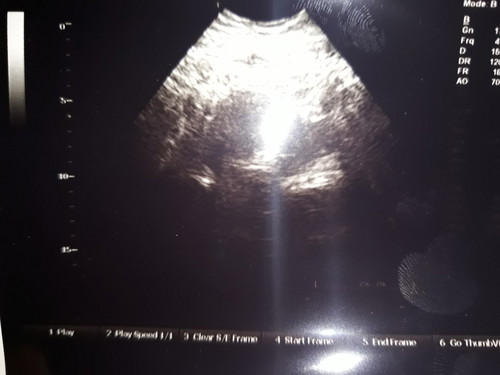

Telat 2 bulan tapi masih negative.. di USG katanya ada penebalan. Badan aku berisi perut agak buncit apa ketutup lemak yahh ??? hmm do'ain yah bunda bunda mudah2an saya cepat di kasih momongan ? aamiin .